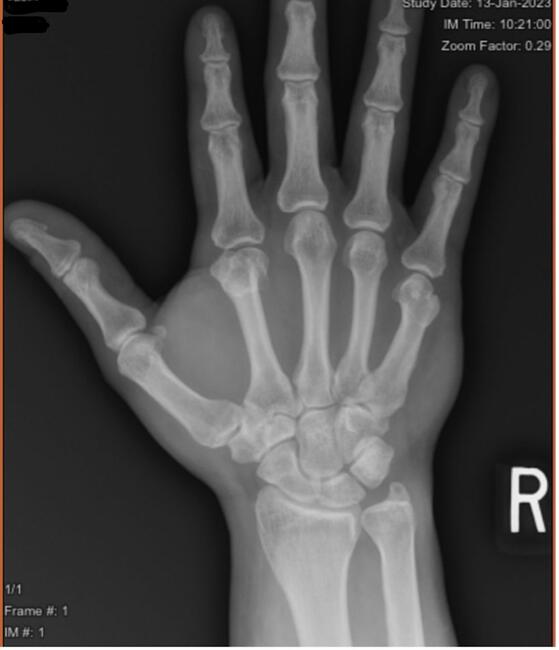

A 39-year-old male presented with a right index finger metacarpal neck malunion with a 30-degree extensor lag and an ulnar malrotation of the digit (Figures 1 and 2) after a fracture 8 months prior. The patient underwent right index finger metacarpal lengthening using iliac crest tricortical bone autograft, right index finger metacarpal joint dorsal and volar capsulectomy, as well as extensor tenolysis and A1 pulley release. A single-stage metacarpal lengthening was achieved with intercalary structural iliac bone graft and intramedullary screw. At 2-week follow-up, the patient had achieved length restoration that resolved extensor lag, reestablished cascade, and had appropriate rotation. At 3-month follow-up, the patient had achieved osseous union and maintained normal cascade of his hand with the ability to make a composite fist. In this article, we present this novel technique for single-stage metacarpal lengthening.

Figure 1. Preoperative posterior-anterior X-ray image of right hand with index finger metacarpal malunion.